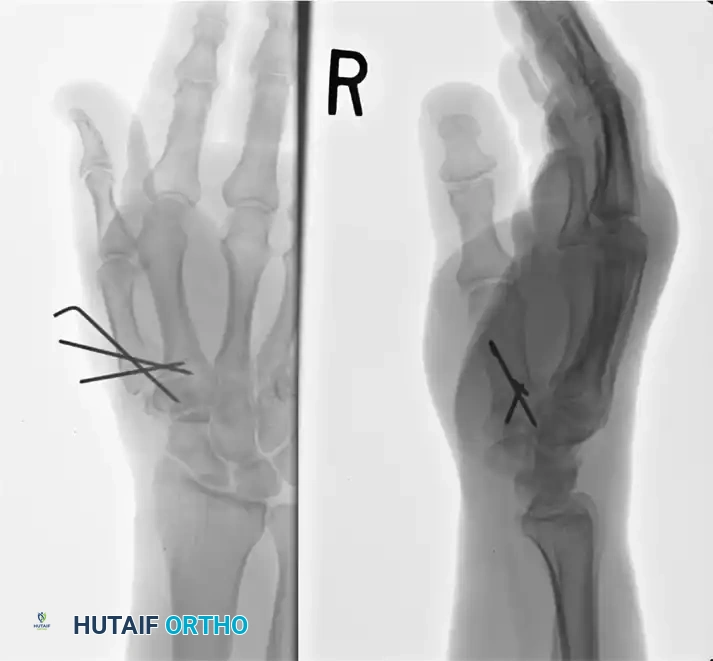

Preoperative radiograph demonstrating a highly comminuted, intra-articular fracture of the first metacarpal base (Rolando variant) with significant axial shortening and articular splaying.

Postoperative radiograph demonstrating successful reconstruction. The articular segments were initially reduced and stabilized with 0.035-inch K-wires, followed by rigid metacarpal-trapezial transarticular pinning utilizing a 0.062-inch K-wire to maintain length and alignment.